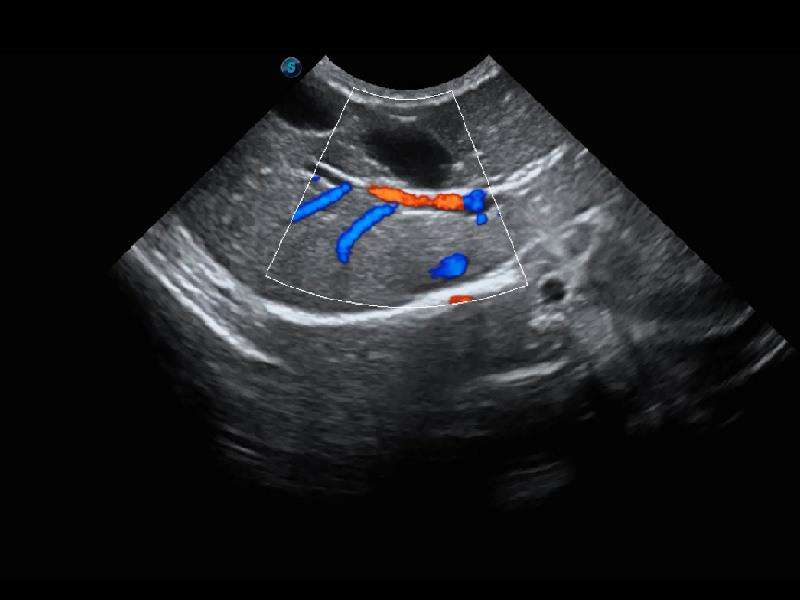

ProPet 60 作為一款高端臺(tái)式動(dòng)物超聲設(shè)備,為動(dòng)物醫(yī)生的日常診斷提供了一系列貼合動(dòng)物臨床需求、解決臨床實(shí)際問題的高級成像功能。憑借全系列高清探頭,滿足醫(yī)生對腹部、心臟、生殖、淺表、肌骨等成像的所有需求,切實(shí)幫助您提升檢查效率,提高診斷信心。